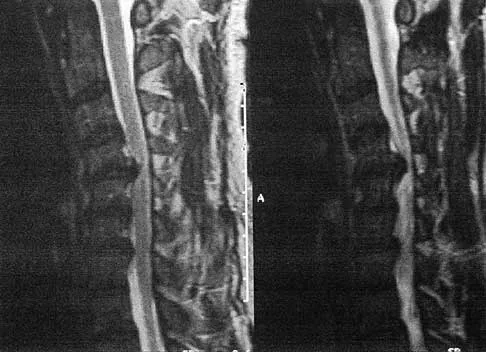

A 40-year-old man has a painless mass around his left ankle. He notes minimal growth over the past year. An MRI scan is shown in Figure 73a, and biopsy specimens are shown in Figures 73b and 73c. What is the most likely diagnosis?

Explanation

The biopsy specimen is a low-power view of a soft-tissue sarcoma with a biphasic pattern of epithelial cells and fibrous spindle cells that are typical of a synovial sarcoma. A deep, painless soft-tissue mass greater than 5 cm in size is suspicious for a sarcoma. The imaging in this patient is indeterminate and the patient requires a biopsy for an accurate diagnosis. The biopsy reveals a tumor with a biphasic appearance consistent with a synovial sarcoma. These tumors are slow growing, occur primarily in the lower extremities, and are found in a younger demographic population compared to malignant fibrous histiocytoma and liposarcoma. They can occur in a biphasic pattern with clumps of epithelial cells and fibrous spindle cells or in a monophasic pattern. Synovial sarcomas stain positively for keratin. Keratin is positive in nearly all biphasic types and in many tumors of the monophasic fibrous type. Sixty percent of these tumors are found in the lower extremity. The area around the knee is the most common location, followed by the ankle and foot. Epithelioid and clear cell sarcomas are found associated with tendon sheaths of the hand and feet and are generally smaller in size. Epithelioid sarcoma may resemble granulomatous inflammation histologically; clear cell sarcoma is composed of nests of clear cells with occasional multinucleated giant cells. Pigmented villonodular synovitis is found within the synovium and is characterized by a villous histologic appearance with hemosiderin-laden macrophages. Malignant fibrous histiocytoma has a storiform histologic pattern with an abundance of pleomorphic cells. Enzinger FM, Weiss SW: Soft Tissue Tumors, ed 3. St Louis, MO, Mosby, 1995, p 757.